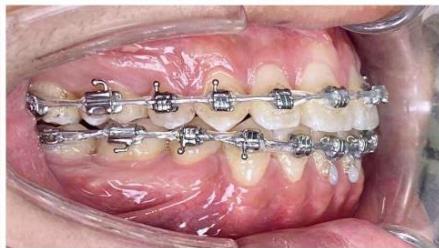

Figure 8: Space closure performed by segmented loop mechanics for canine retraction, followed by anterior space closure using a retraction arch with three-dimensional torque control

### c) Incisor Retraction using Segmented Mechanics

After completion of canine retraction, the incisor segment was retracted using segmented mechanics according to the Ricketts Bioprogressive philosophy. Retraction arches in both arches were designed to achieve three objectives simultaneously: (i) controlled incisor retraction; (ii) activation of an intrusive component of approximately 2-3 mm to counteract anterior tooth extrusion, which is particularly critical in high-angle patients; and (iii) generation of strong and stable positive torque to achieve three-dimensional control of incisor root movement, especially in the mandibular arch [19-21]. The retraction arches were activated at a rate of approximately 1.5 mm per month while maintaining torque and vertical control.

During the finishing phase, the ART torque spring was continuously maintained in the mandibular incisor region to reduce secondary negative torque and to assist in directing the incisor roots into cancellous bone, thereby protecting the labial cortical plate during the stage when retraction forces generate the most unfavorable moments [22-24].